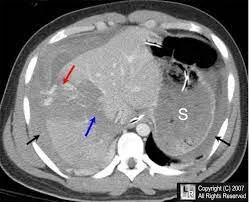

Diagnosis

Unstable pt w/ positive FAST- exploratory laparotomy

Stable- CT abdomen w/ IV contrast

perihepatic hematoma, hemoperitoneum, parenchymal disruption